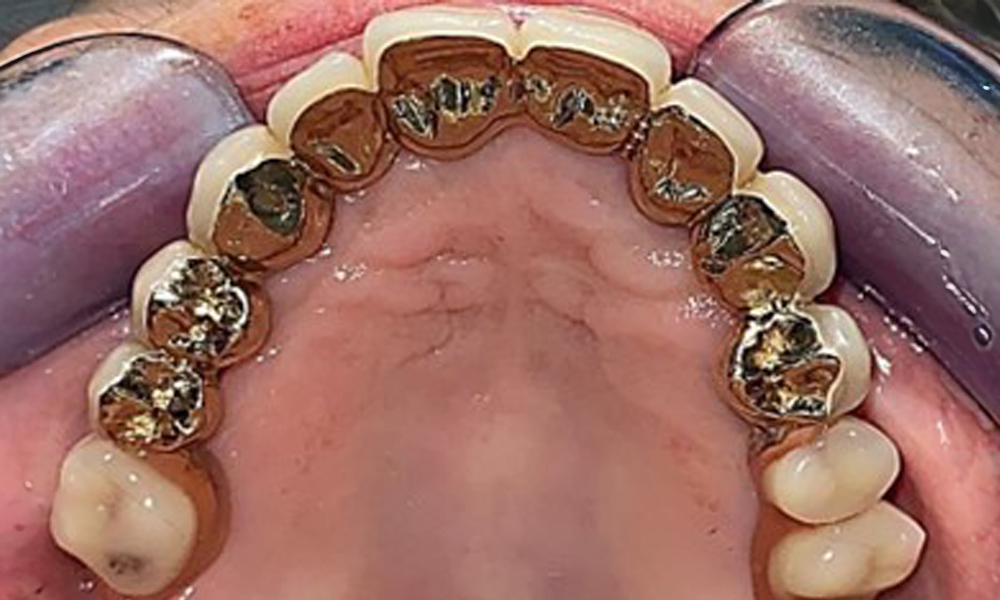

Occlusal view: Maxilla with removable, palateless denture.

Fig. 3: Occlusal view: Maxilla with removable, palateless denture.

Occlusal view of the mandible.

Fig. 4: Occlusal view of the mandible.

The dental findings are as follows: Combined removable implant and tooth-supported telescopic prostheses on implants 15, 13, 21, 23, 24, 25 and tooth 11 (Fig. 1, Fig. 2, Fig. 3). The patient was fitted with a fixed mandibular denture. Adequate bridges were present over 37 to 34 and 45 to 47 (Fig. 4), the crown margins were intact and there were no active caries. A composite filling with a marginal gap was present on tooth 43. There was mandibular gingival recession, exposing 1 to 3 mm of root surface. This also applies to 11.